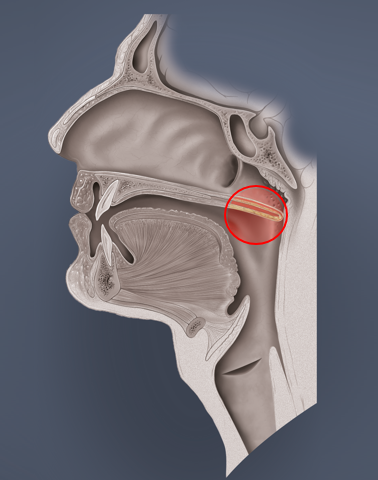

- Eustach’sche Röhre (Tuba auditiva, engl. Eustachian tube)

Die Tube ist eine 30 – 35 mm lange, mit Flimmerepithel ausgekleidete, Röhre, die das Mittelohr und den Nasenrachenraum verbindet. Ohne eine ausreichende Belüftungsfunktion ist der Druckausgleich unmöglich, da dies der einzige Zugang zum Mittelohr ist. Im Normalzustand ist die Tube geschlossen, öffnet sich jedoch beim Schlucken, Gähnen oder bestimmten Lauten und natürlich beim Druckausgleich.

Die Valsalva-Technik

Antonio Maria Valsalva war ein italienischer HNO-Arzt (1666 – 1723). Die nach ihm benannte Technik sollte bei Mittelohrentzündungen die Belüftung und den Abtransport des Eiters oder Schleims aus dem Mittelohr durch die Tube begünstigen. Dabei bediente er sich der Bauchpresse, d. h. Anspannung der Bauchmuskulatur. Die Valsalva-Technik basiert ergo auf recht hohem Druck und verringert das Lungenvolumen. Die Mundhöhle wird mit dem T-, Ca- oder H-Lock verschlossen (s. o.). Dieser hohe Druck ist medizinisch nicht immer erwünscht. Wenn beispielsweise ein PFO (persistierendes Foramen ovale) vorliegt, können dadurch Mikroblasen von der rechten Herzhälfte in die arterielle linke Herzhälfte gedrückt werden und so das Risiko für eine Dekompressionserkrankung erhöhen. Zudem kann bei zu forcierten Versuchen mit der kraftvollen Bauchmuskulatur ein Ödem zum Flimmerepithel der Tube „hingedrückt“ werden. Danach ist der Druckausgleich dann nur noch schwer möglich. Bei zu hohem Druckgradienten legen sich zudem die Wände der Tube aneinander und eine Öffnung ist nicht mehr oder nur sehr erschwert möglich.

Die Frenzel-Technik

Der deutsche Luftwaffenarzt Walter Gotthold Frenzel entwickelt diese Technik für den Druckanstieg in Kampffliegern bei schneller Höhenabnahme. Diese Technik basiert auf „mechanischem Druck“, da hierbei die Luft im Mundraum durch die Zunge Richtung hinten oben in den Nasenraum gedrückt wird. Dabei kann die Zunge in der T-, Ca- oder H- Stellung sein. Die Frenzel-Technik ist eine sanfte Methode um den Druckausgleich zu bewältigen, da weniger Druck aufgebaut wird. Manchen Tauchern fällt es dadurch leichter die Tube zu öffnen. Das Risiko eines Shunts von Mikroblasen, bei vorliegendem PFO, auszulösen ist geringer als beim Valsalva-Manöver. Die Frenzel-Technik stellt jedoch keinen Schutz davor dar!

Sowohl beim Valsalva- als auch beim Frenzel-Manöver muss der weiche Gaumen natürlich offen sein und den Weg zum Nasenraum freigeben. Beim Valsalva ist die Stimmritze offen, beim Frenzel geschlossen (s. Bilder oben).

Da hierbei die beiden kleinen Muskeln (Tensor und Levator veli palatini) stark involviert sind, machen wir uns zunächst die anatomische Lage dieser Muskeln klar. Der Musculus levator veli palatini kommt vom Felsenbein (der Knochen hinter dem Ohr) und setzt am weichen Gaumen an, den er bei Anspannung nach hinten oben bewegt. Dabei nimmt er den Eingang der Tube mit, der sich dabei öffnet. Der Musculus tensor levi palatini kommt auch von einem Schädelknochen, dem sogenannten Keilbein und setzt am weichen Gaumen an. Wenn er in Aktion tritt, spannt er den weichen Gaumen an und versteift dabei die vordere seitliche Wand der Tube, die dadurch in geöffnetem Zustand bleibt.

Zu 1.) False

Der „False“ (= falsche) Hands-Free-Druckausgleich wird ähnlich wie der Frenzel durch die Zunge durchgeführt. Die Nase ist dabei lediglich durch die sehr festsitzende Maske verschlossen. Die Luft wird durch die in T-Stellung befindliche Zunge langsam nach hinten oben „gestempelt“. Durch das abnehmende Volumen im Mundraum steigt der Druck und die Luft entweicht über den Nasenraum Richtung Tube. Im Zusammenspiel mit den beiden kleinen Muskeln (Musculi tensor und levator veli palatini) öffnet sich die Tube und der Druckausgleich im Mittelohr kann stattfinden. Bei offenem weichen Gaumen ist die Glottis hierbei verschlossen.

Zu 2.) Toynbee

Diese Technik wurde nach dem britischen HNO-Arzt Joseph Toynbee benannt (1815 – 1866). Er fand heraus, dass die Muskeln tensor und levator veli palatini beim Schluckakt die Tube öffnen. Bei manchen Tauchern gelingt er Druckausgleich rein durch Schlucken.

Zu 3.) Pure

Mit ein bisschen Übung kann man lernen die für die Tubenöffnung verantwortlichen Muskeln bewusst anzusteuern. Das kann man durch willentliche Anspannung der Muskulatur um das Kiefergelenk und des weichen Gaumens ausprobieren. Ihr könnt auch die Kehlkopfmuskeln zu Hilfe nehmen. Das muss man ausprobieren. Bei erfolgreicher Anspannung unserer zwei kleinen Tuben-Hilfsmuskeln spürt ihr eine Druckveränderung im Mittelohr und wisst, dass es funktioniert hat.